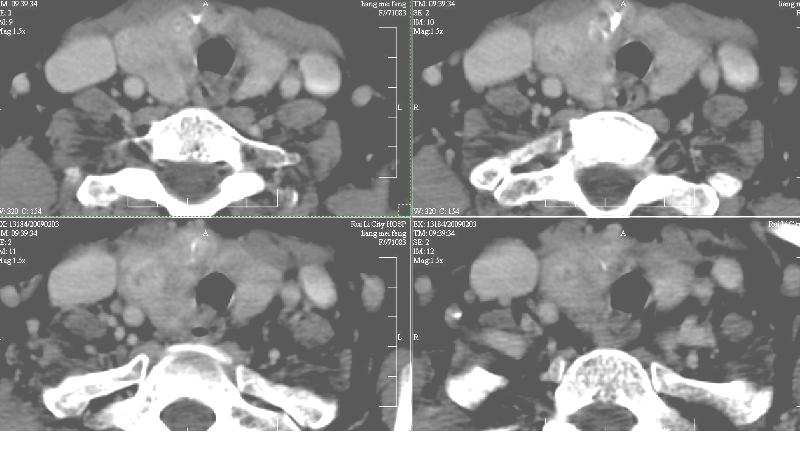

双侧甲状腺稍肿,右侧触及包块,随吞咽上下活动。 1、双侧甲状腺肿(摄碘率降低)。2、右侧甲状腺多发腺瘤,必要时增强。平扫

增强:1、双侧甲状腺肿。2、平扫甲状腺内多发占位病变,增强显示不清楚,境界欠清,请结合临床考虑甲状腺瘤。